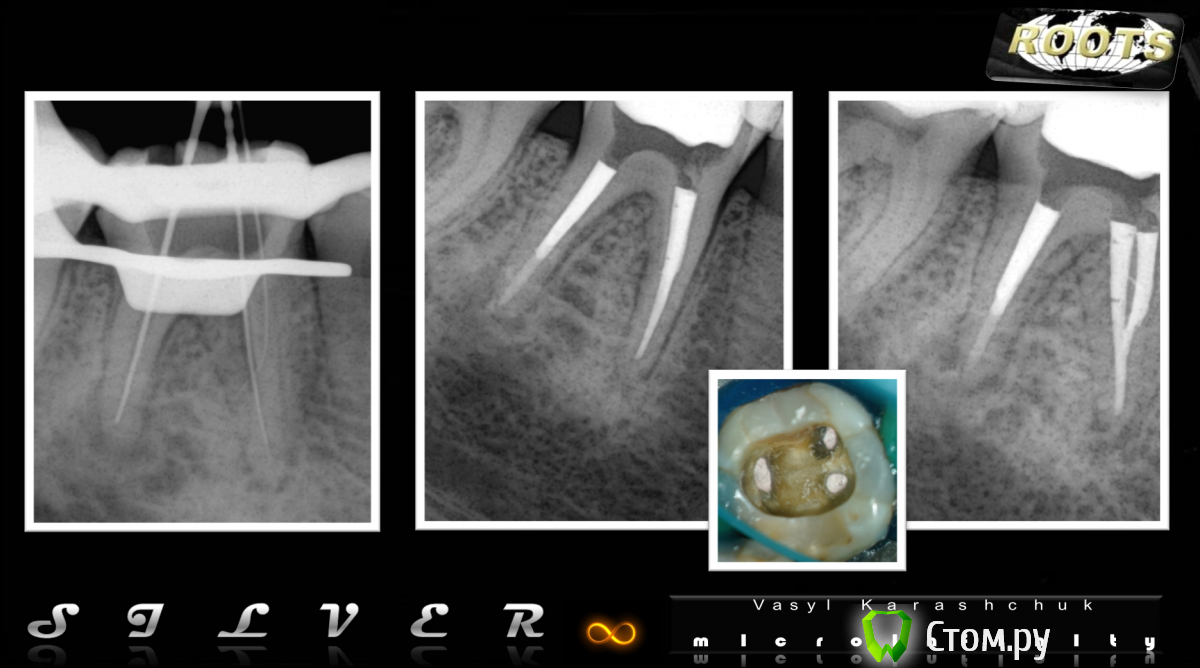

punkrat Опубликовано 6 сентября, 2014 Автор Поделиться Опубликовано 6 сентября, 2014 Коллеги решил дополнить и расширить свой вопрос.1) как альтернативу Про Рут сейчас пользуем Рутдент, материал сравнительно предсказуем, удобен в работе быстро, опять же сравнительно, твердеет. У кого-нибудь есть опыт и отдаленные результаты по работе с этим материалом.2) и еще вопрос за который мне стыдно, но я задам его. До сих пор использовал цементы на основе МТА и подобные для закрытия, скажем так, обозримых перфораций, настало время двигаться дальше, а именно начать паковать апикальную треть корня при невозможности полноценно осушить верхушку ( в связи с различными причинами). Пытался несколько раз, но остался недоволен результатом категорически, стенки мазались излишками материала, в процессе работы не был уверен в доведении материала до верхушки, приходилось делать Рг, потом допаковывать и перепаковывать и т.д. Пожалуйста, если не трудно, подскажите подробный алгоритм работы в данном случае, чтобы все получалось предсказуемо и аккуратно, вот например как дистальный канал на этом снимке: http://rosmicro.ru/wp-content/uploads/2014/04/%D0%A0%D0%B8%D1%81%D1%83%D0%BD%D0%BE%D0%BA32.png Заранее премного благодарен. Ссылка на комментарий

Каплан Опубликовано 6 сентября, 2014 Поделиться Опубликовано 6 сентября, 2014 (изменено) http://imageshack.com/a/img661/3176/OIH8SR.jpg Это мне кажется перебор Изменено 6 сентября, 2014 пользователем Каплан Ссылка на комментарий

punkrat Опубликовано 6 сентября, 2014 Автор Поделиться Опубликовано 6 сентября, 2014 (изменено) Это мне кажется перебор На самом деле пусть даже уйдет разрежение костной ткани после закрытия перфорации (наверняка оно там было)) и пусть этот товарищ этим даже будет гордиться. Но зуб это функциональный орган и он испытывает нагрузку и довольно-таки не малую и если бывают случаи раскола даже витальных зубов, то что уж говорить про этот латаный-перелатаный пенек, какую нагрузку он сможет вынести? Совершенно непрактичная затея, короче... "Головокружение от успехов", как говорил товарищ Сталин))) Изменено 6 сентября, 2014 пользователем punkrat 5 Ссылка на комментарий

punkrat Опубликовано 11 сентября, 2014 Автор Поделиться Опубликовано 11 сентября, 2014 (изменено) и все-таки, коллеги, подскажите мануал паковки "Прорутподобными" материалами апикальной части канала (чтобы как на фото было в дистальном), подскажите из вашего опыта или есть где-то в открытых источниках статья или видео. Вроде ерунда, а хорошо не выходит, а хочется чтоб выходило, ибо дело ответственное. Изменено 11 сентября, 2014 пользователем punkrat Ссылка на комментарий